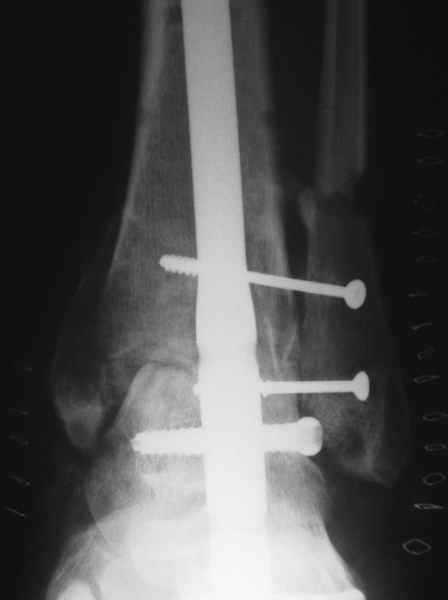

Nail arthrodesis for failed pilon fracture is good solution.

My example